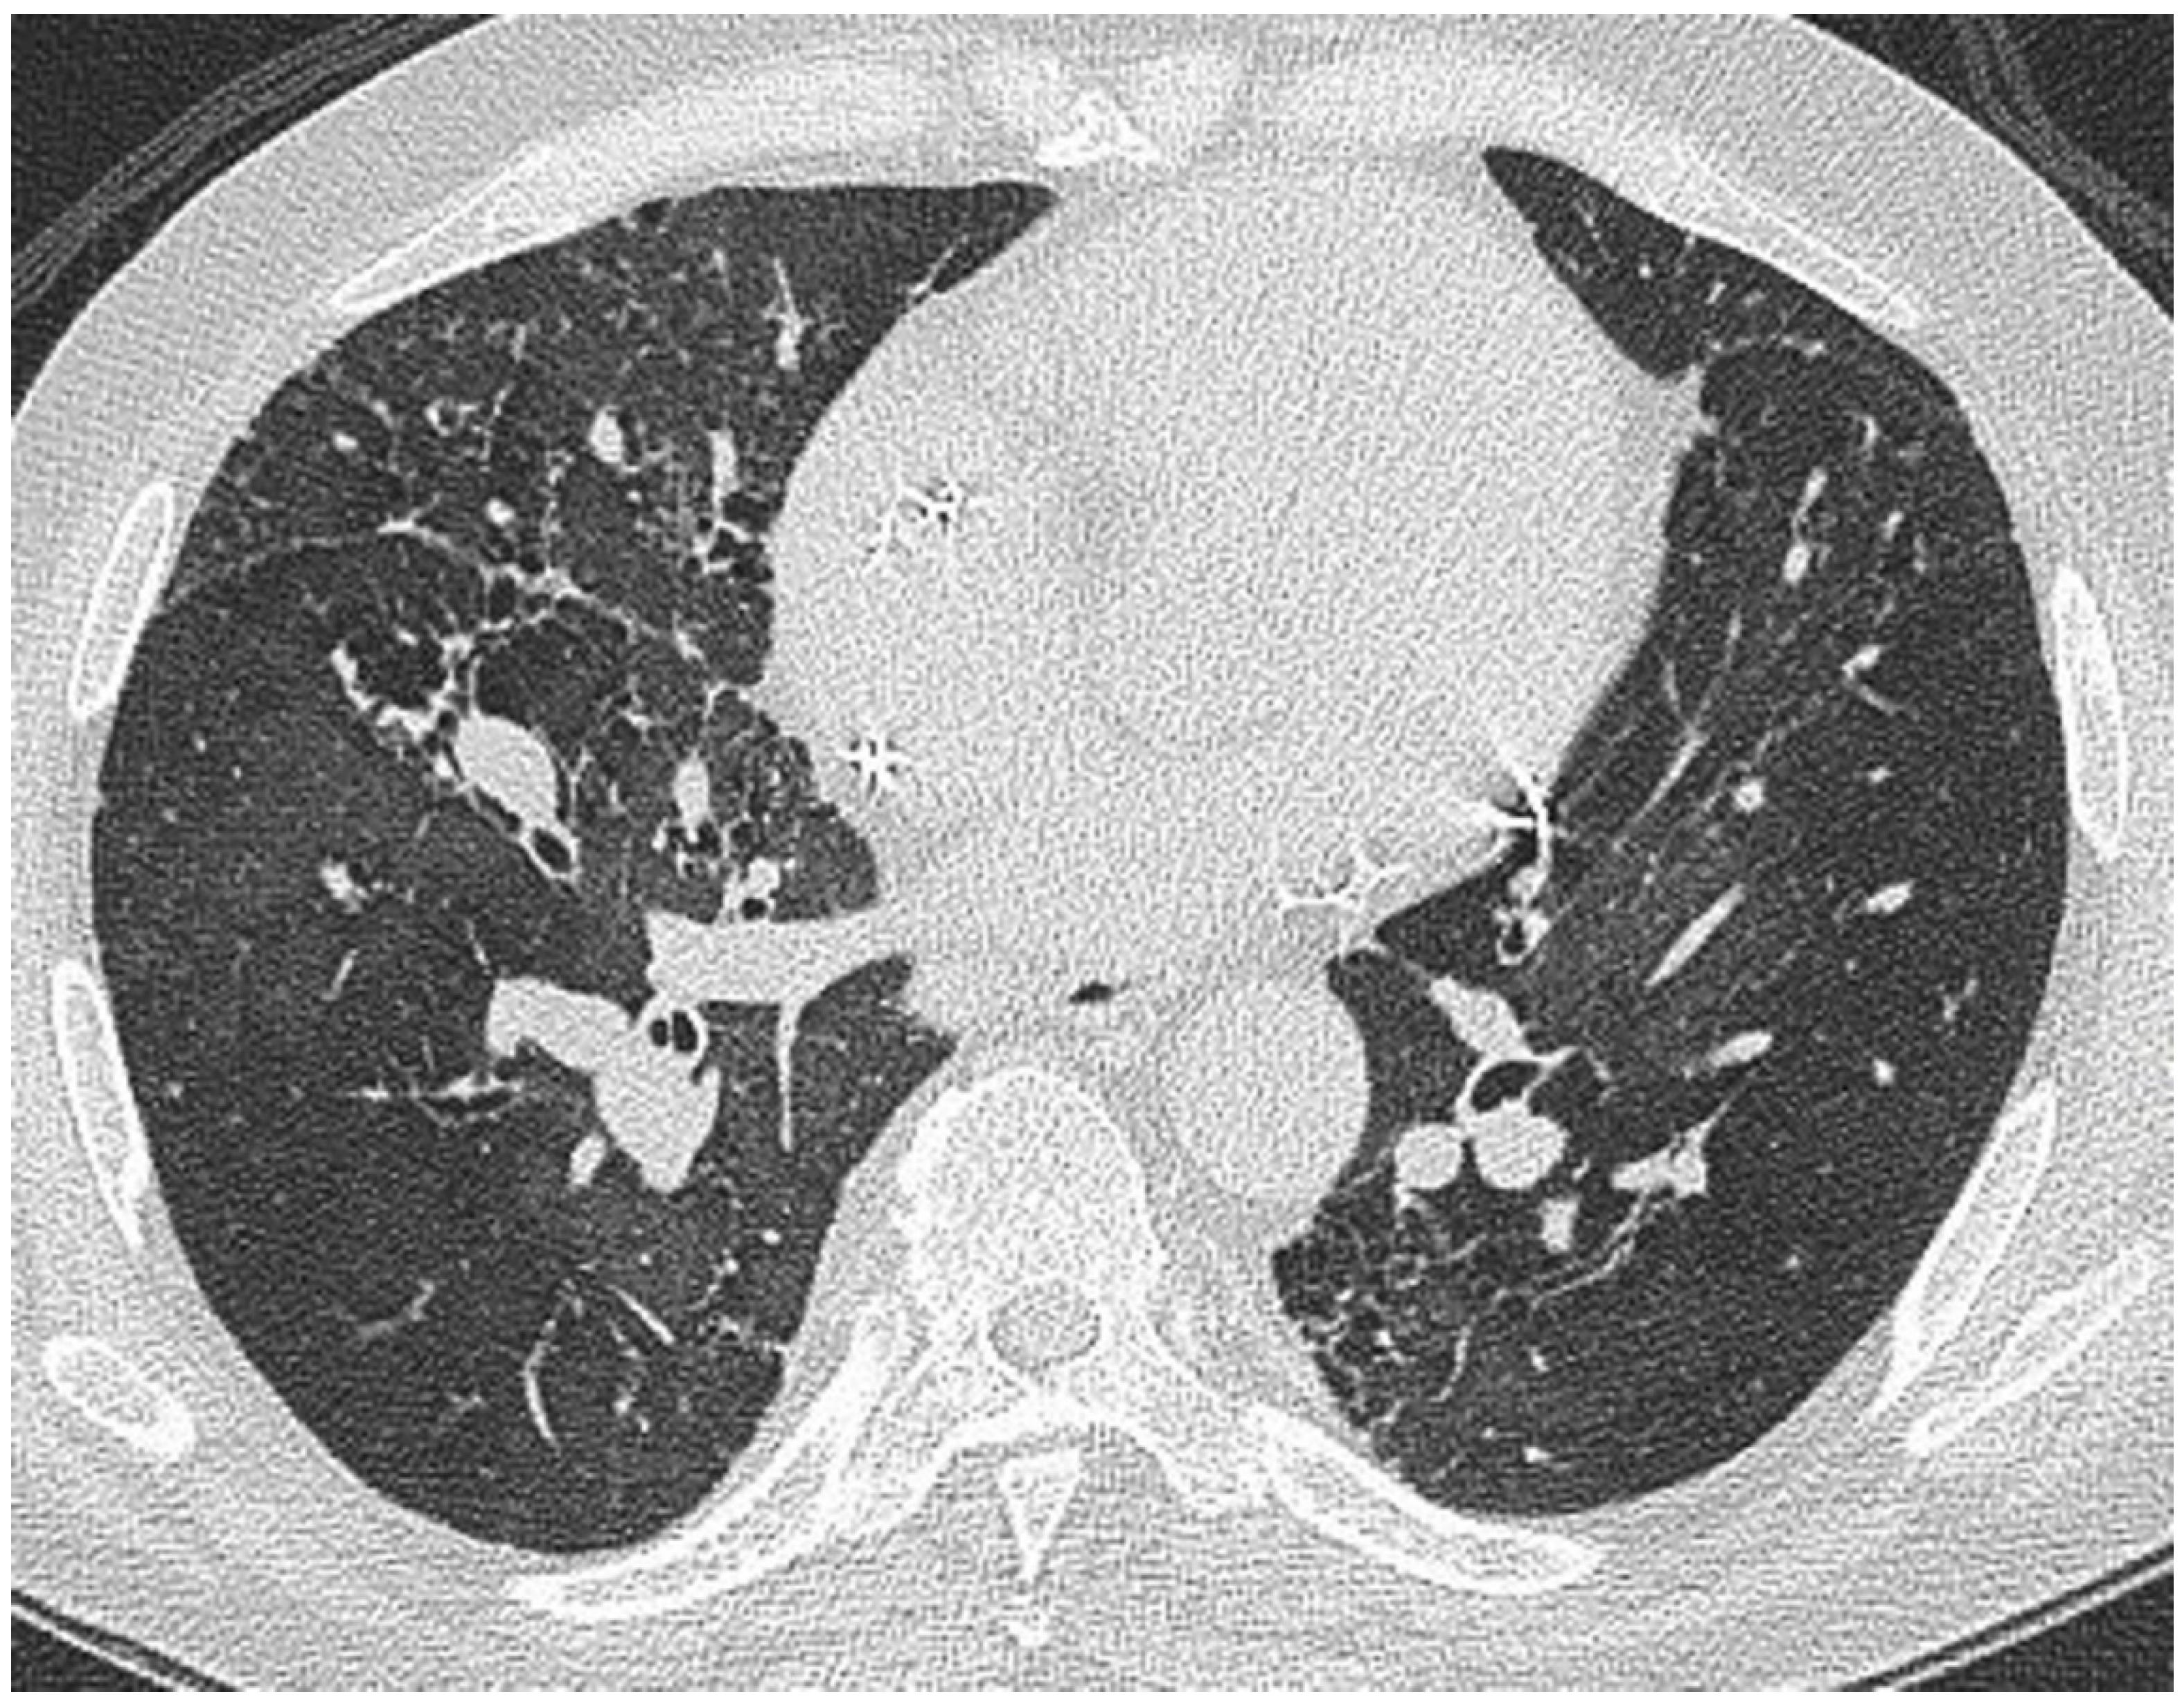

Lung nodules on CT are the most widely recognised and common CT manifestations of sarcoidosis [7,47,48]. In a small series of 45 patients with suspected or known sarcoidosis, nodules were present in 80% [7]. In a larger study of 95 patients by Remy-Jardin et al., a nodular pattern was present in 93% [49]. In the classical case, bronchocentric micronodules (measuring 1–3 mm in diameter), are seen in the mid and upper zones. Lung nodules, corresponding to aggregates of microscopic epithelioid granulomata [50], may be diffusely distributed throughout the lungs or, less frequently, localised to one or several focal areas. The predilection for the axial interstitium (i.e., surrounding bronchovascular bundles), accounts for the readily recognisable thickened, irregular perihilar and peribronchovascular appearance [48] (Figure 2). Irregular or nodular thickening of interlobular septa—mimicking lymphangitis carcinomatosa—is recognised but is rarely a dominant feature [51,52,53].

CT at the level of the carina in the same patient as in Figure 1. There is a roughly symmetrical bronchocentric micronodular infiltrate. More centrally, there is dense parenchymal opacification caused by conglomeration of nodules around the bronchovascular structures.